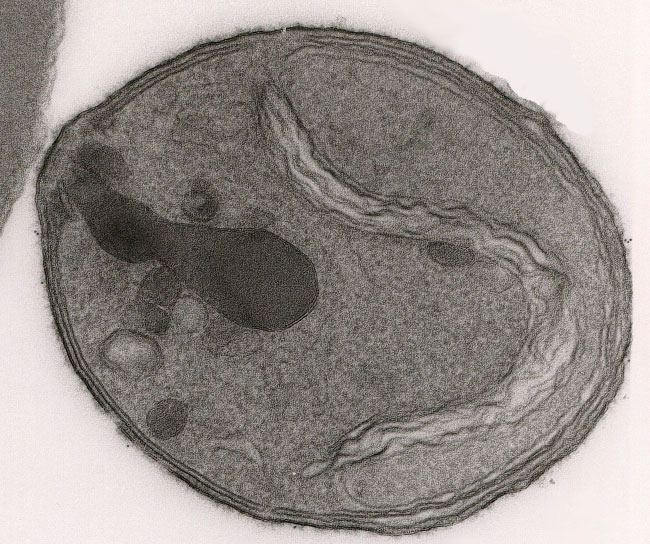

gd/merozoit.jpg